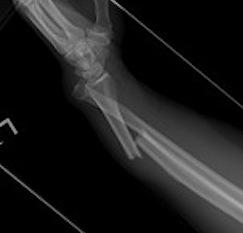

Xray

DRUJ disruption

- widened space between radius and ulna on AP

- dorsal subluxation / dislocation of ulna on lateral

- radial shortening > 5 mm

- ulna styloid fracture

Shortening of radius with disruption of DRUJ on lateral

Widening of interval between radius and ulna / clear disruption of DRUJ

Concern for disruption of DRUJ on lateral